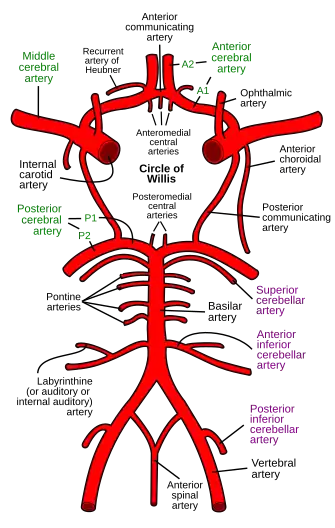

Pontine arteries

| Pontine arteries | |

|---|---|

Diagram of the arterial circulation at the base of the brain. (Pontine labeled at center left.) | |

| Details | |

| Source | Basilar artery |

| Supplies | Pons |

The pontine arteries are a number of small arteries which come off at right angles from either side of the basilar artery and supply the pons and adjacent parts of the brain. The pontine arteries include the paramedian arteries, the short circumferential, and the long circumferential arteries.[1][a]

- ^ Refer to diagram.